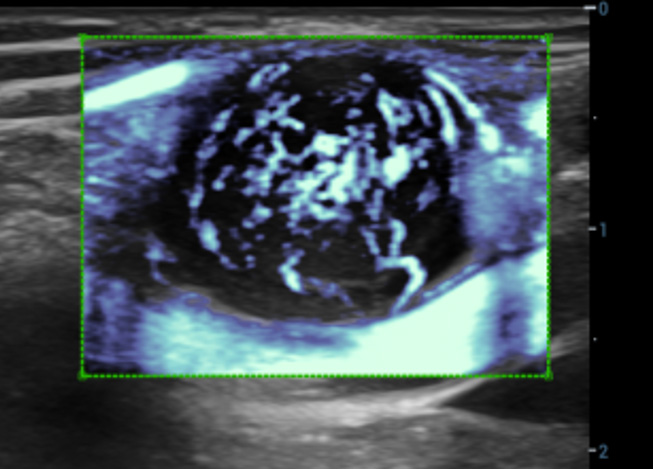

Geavanceerde CEUS

UWN+(Ultra-Wideband Niet-linear) CEUS

CEUS Borst kwaadaardig

Door gebruik te maken van zowel de 2e harmonische als niet-lineaire fundamentele signalen, maaktUWN+ een hoge gevoeligheid van bubbelsignalen en langere contrastperfusie met een lagere MI mogelijk, wat helpt bij tumorbeoordelingen.

UWN+-contrastbeeldvorming

Detecteer en gebruik zowel 2e harmonische als niet-lineaire fundamentele signalen voor het genereren van beelden met:

- Uitstekende agentgevoeligheid, zelfs bij een laag signaal

- Langere perfusietijd met lagere MI

- Betere visualisatie van perfusie van kleine bloedvaten met MFE (Micro Flow Enhancement)